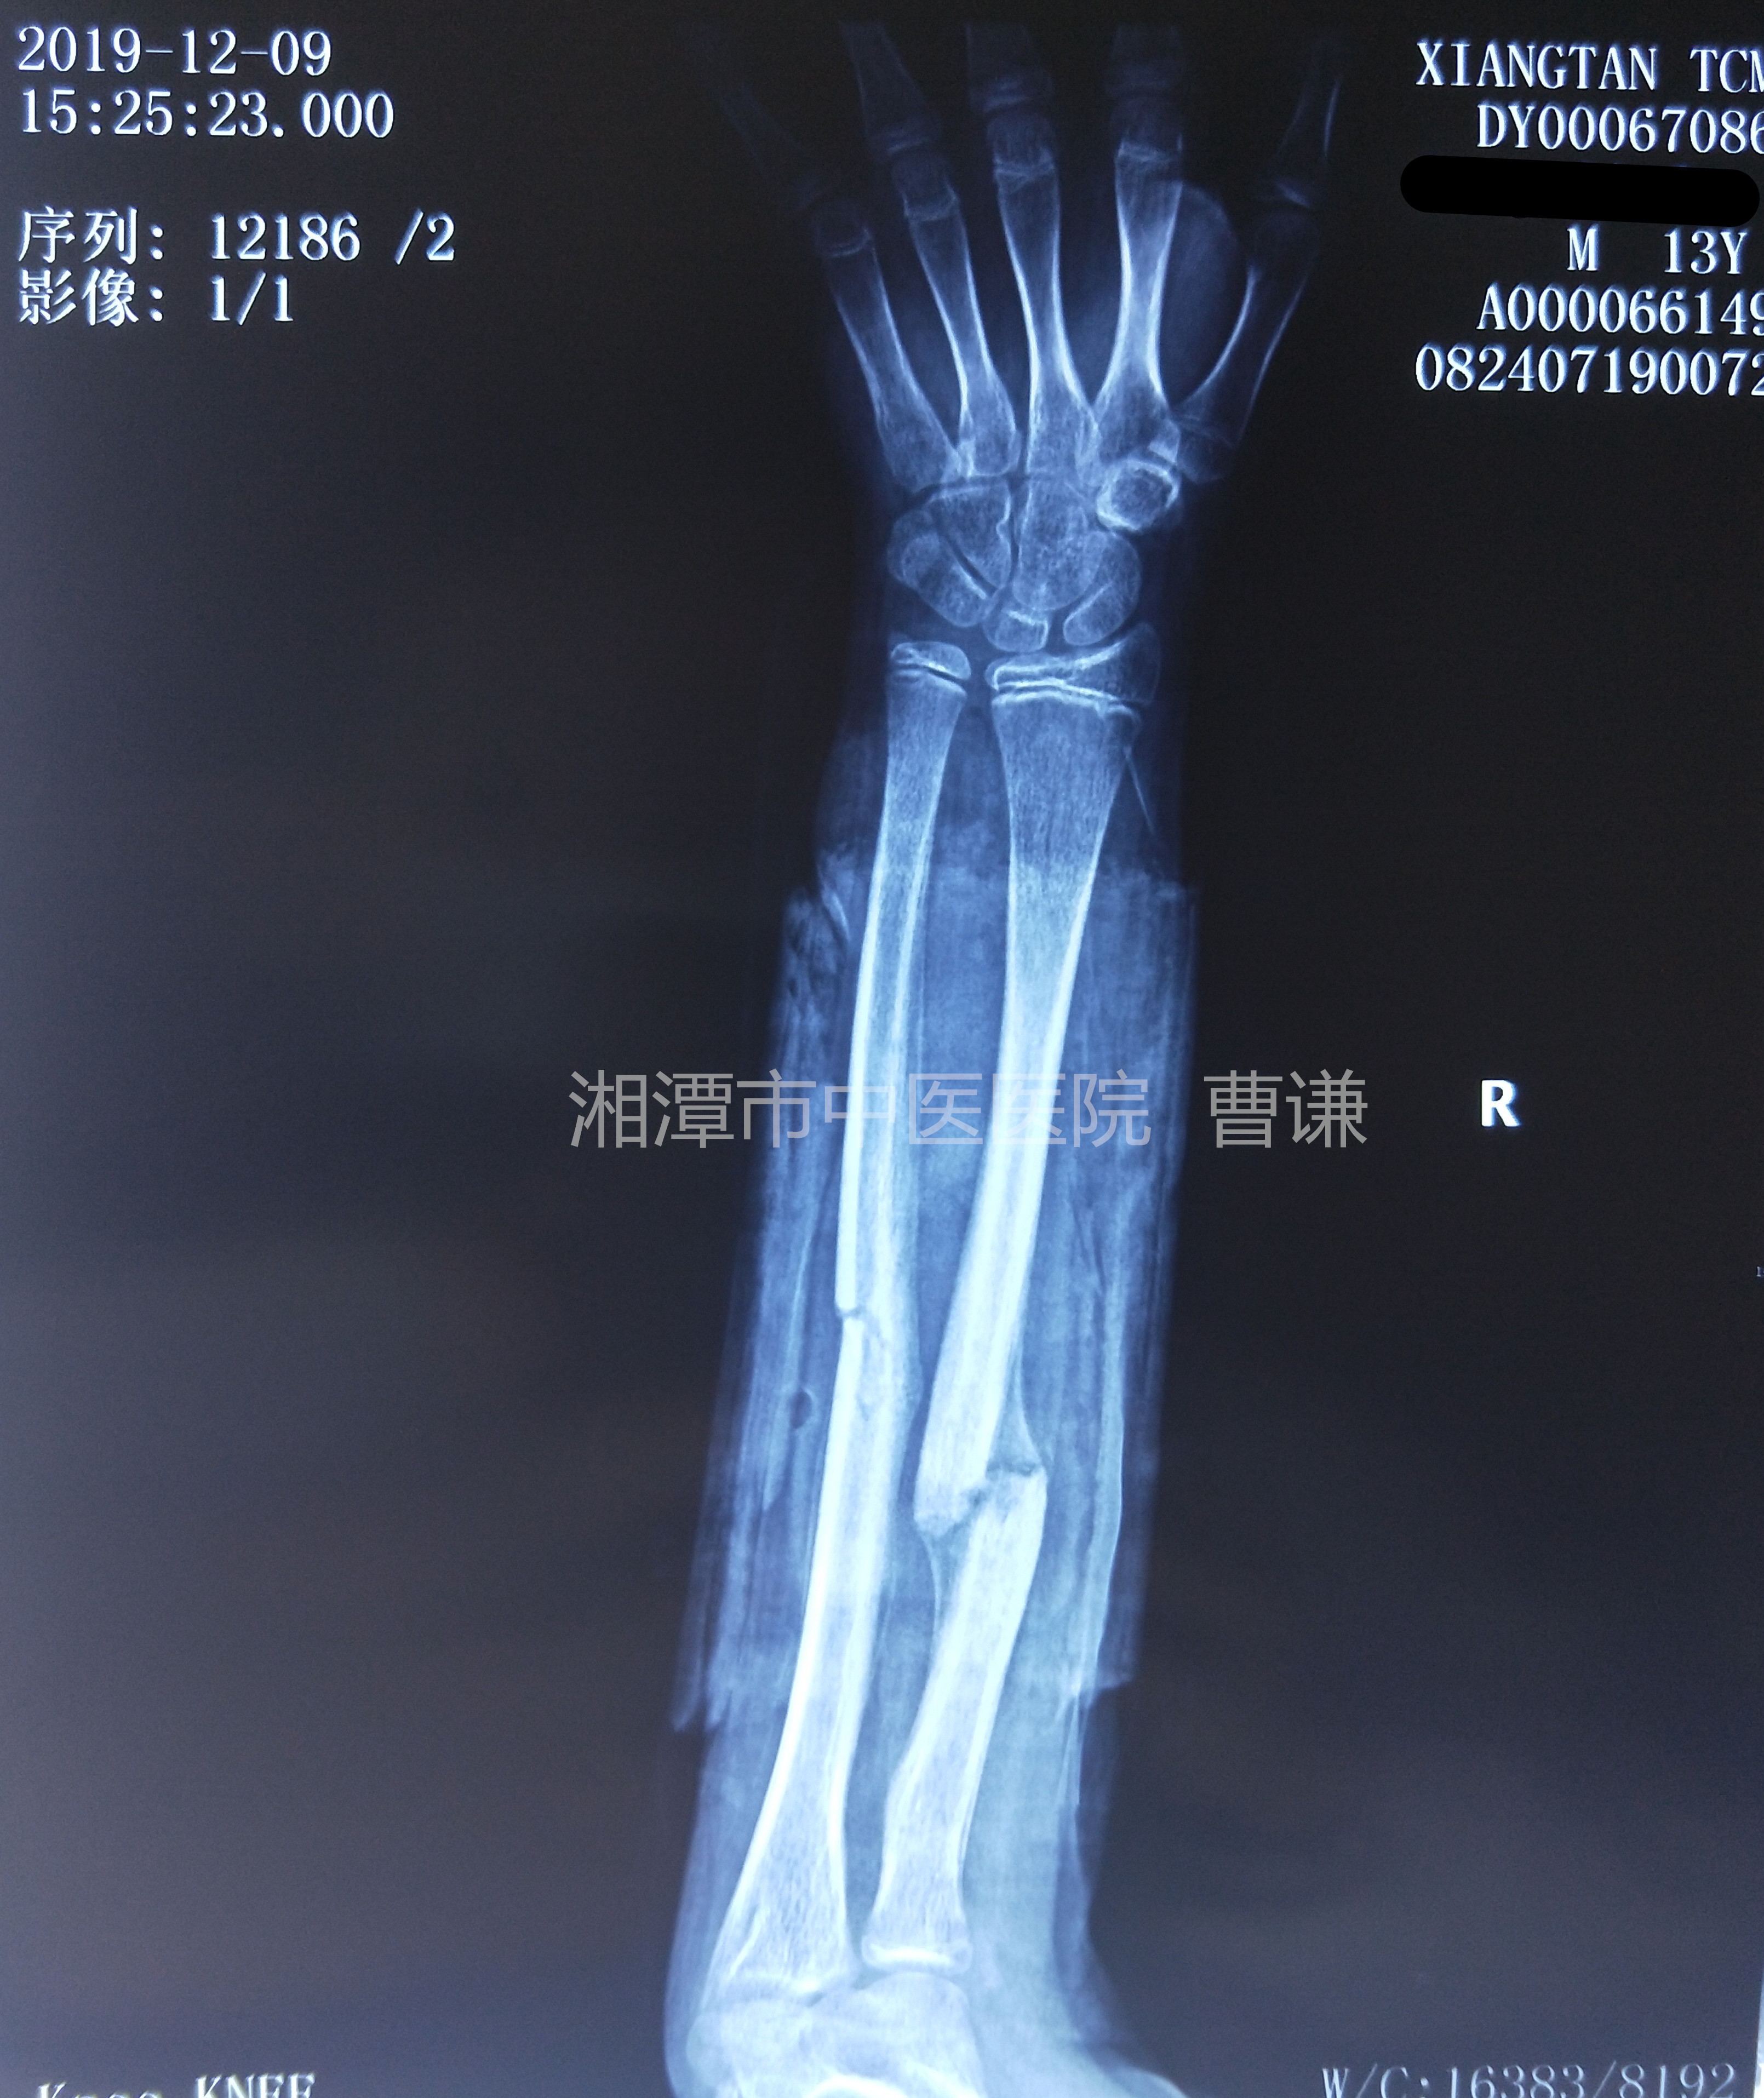

固定一个月后拍片复查见骨痂生长,拆除直角托板,开始肘关节屈伸功能锻炼。